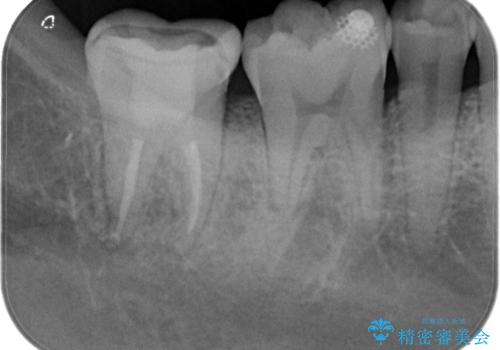

【根管治療】噛んだ時にしみる。最近になってズキズキ痛み、長引く痛みがある

担当医 河口智英